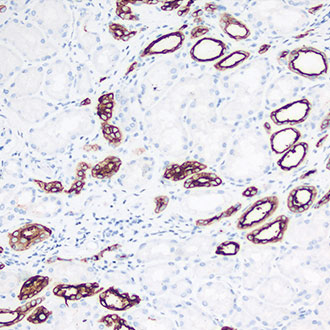

CK7

CK7 -